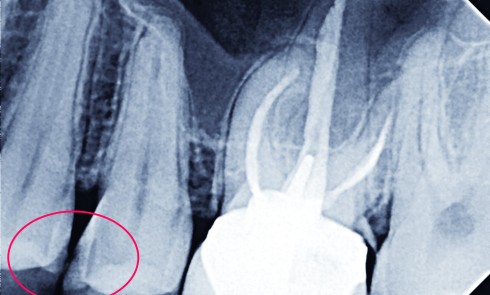

Article réservé à nos abonnés Gestion thérapeutique de lésions carieuses proximales sur dents adjacentes

La gestion thérapeutique des lésions carieuses proximales postérieures se heurte à plusieurs complexités tant diagnostiques que techniques. La multiplicité des...